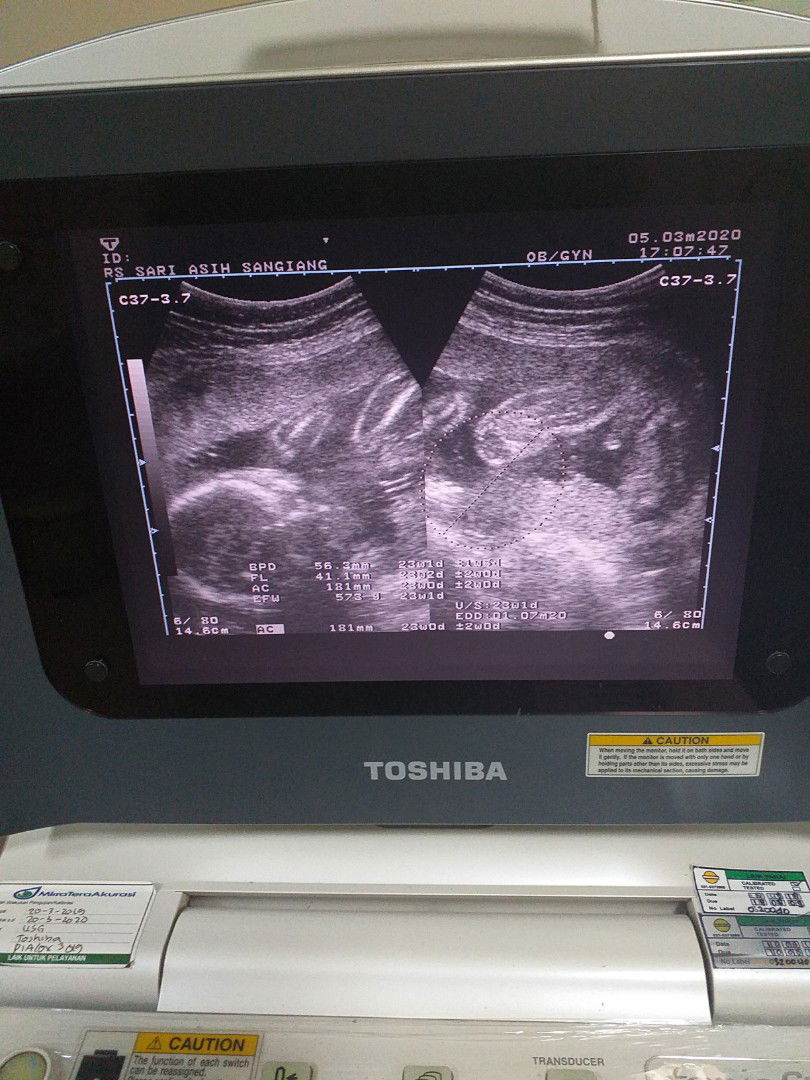

Usg kemarin bun. Udah keliatan jk nya Dan waktu usg dedenya ngangkang hehee. Alhamdulillah semua sehat. Loveyoudedee?